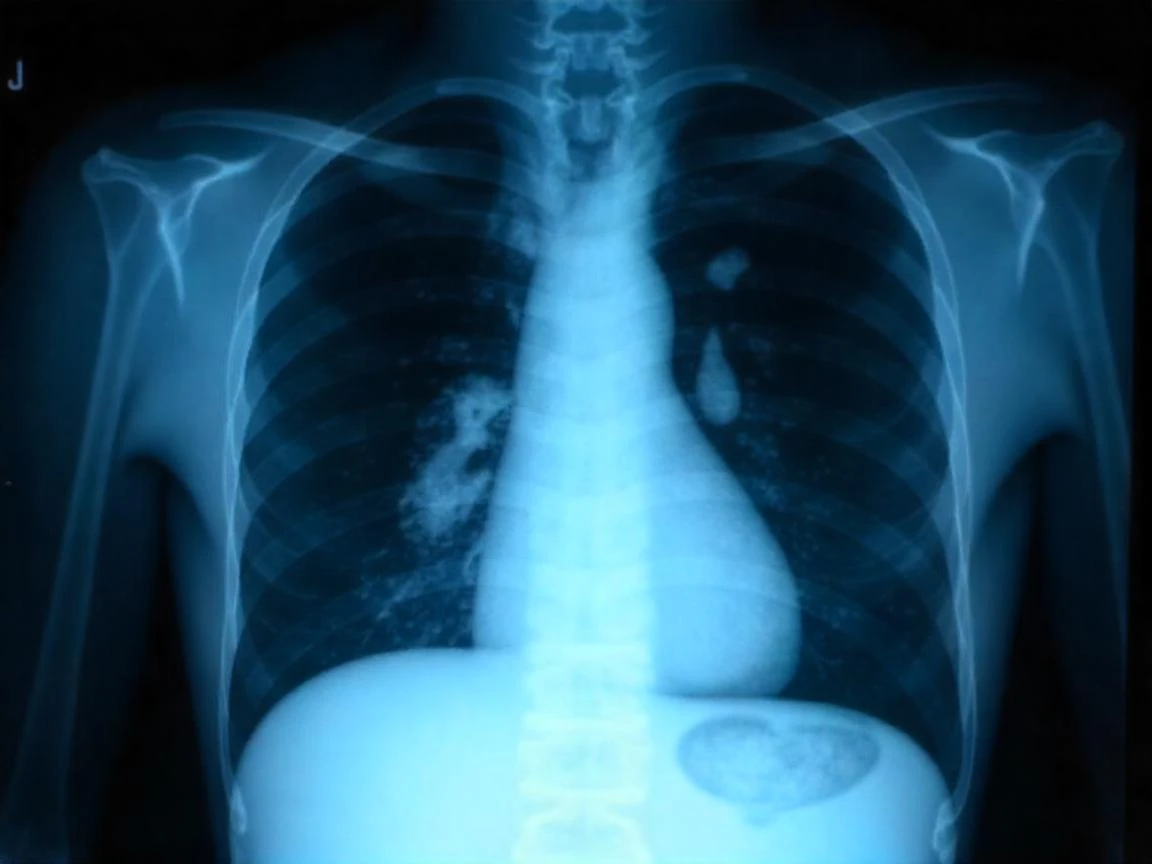

Göğüs Cerrahisi Uzmanı Prof. Dr. Gürhan Öz, akciğer kanseri tedavisinde beslenmenin büyük önem taşıdığını vurgulayarak, hastaların dengeli ve yeterli besin alımının tedavi sürecini olumlu etkilediğini söyledi. Medical Park İzmir Hastanesi'nden Prof. Dr. Öz, akciğer kanseri hakkında önemli bilgiler paylaştı.

Akciğer kanserinin dünya genelinde ve Türkiye'deki yaygınlığına dikkat çeken Prof. Dr. Öz, sigara kullanımının en büyük risk faktörü olduğunu belirtti. Pasif içicilik, hava kirliliği, asbest ve genetik faktörlerin de akciğer kanseri riskini artırdığını ifade etti. Erkeklerde kadınlara oranla 3,5 kat daha fazla görülen bu hastalığın belirtilerinin göz ardı edilmemesi gerektiğini vurguladı.

Prof. Dr. Öz, geçmeyen öksürük, kanlı balgam, nefes darlığı, hırıltılı solunum, ses kısıklığı gibi solunumla ilgili belirtilerin yanı sıra iştahsızlık, kilo kaybı, kronik yorgunluk, göğüs ağrısı ve tekrarlayan akciğer enfeksiyonlarının da akciğer kanseri işaretleri olabileceğini söyledi. İleri evrelerde ise kemik ağrıları, baş ağrısı ve bilinç değişiklikleri gibi belirtilerin görülebileceğini aktardı.